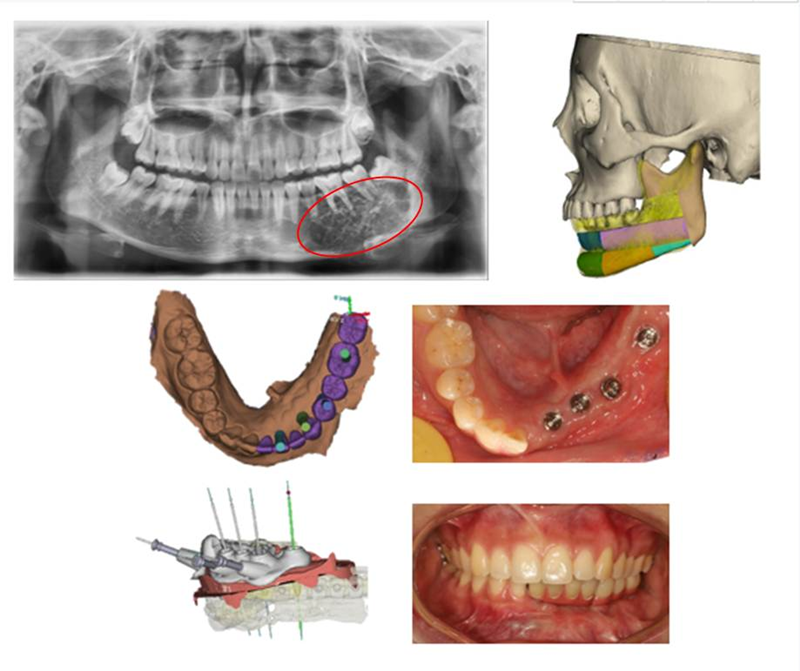

Besides, the MDT includes Tumor-Dental Implant, Tumor Orthognathic-Dental Implant, Tumor-Trauma-Orthognathic-Cleft Lip and Palate Groups. For one patient suffering jaw carcinoma disease, the team performed the surgery of partial mandibular resection, and simultaneous bone graft with implant restoration by using digital technology. This MDT work had both therapeutic and functional benefits, which greatly improved the patient’s occlusal function and living quality.